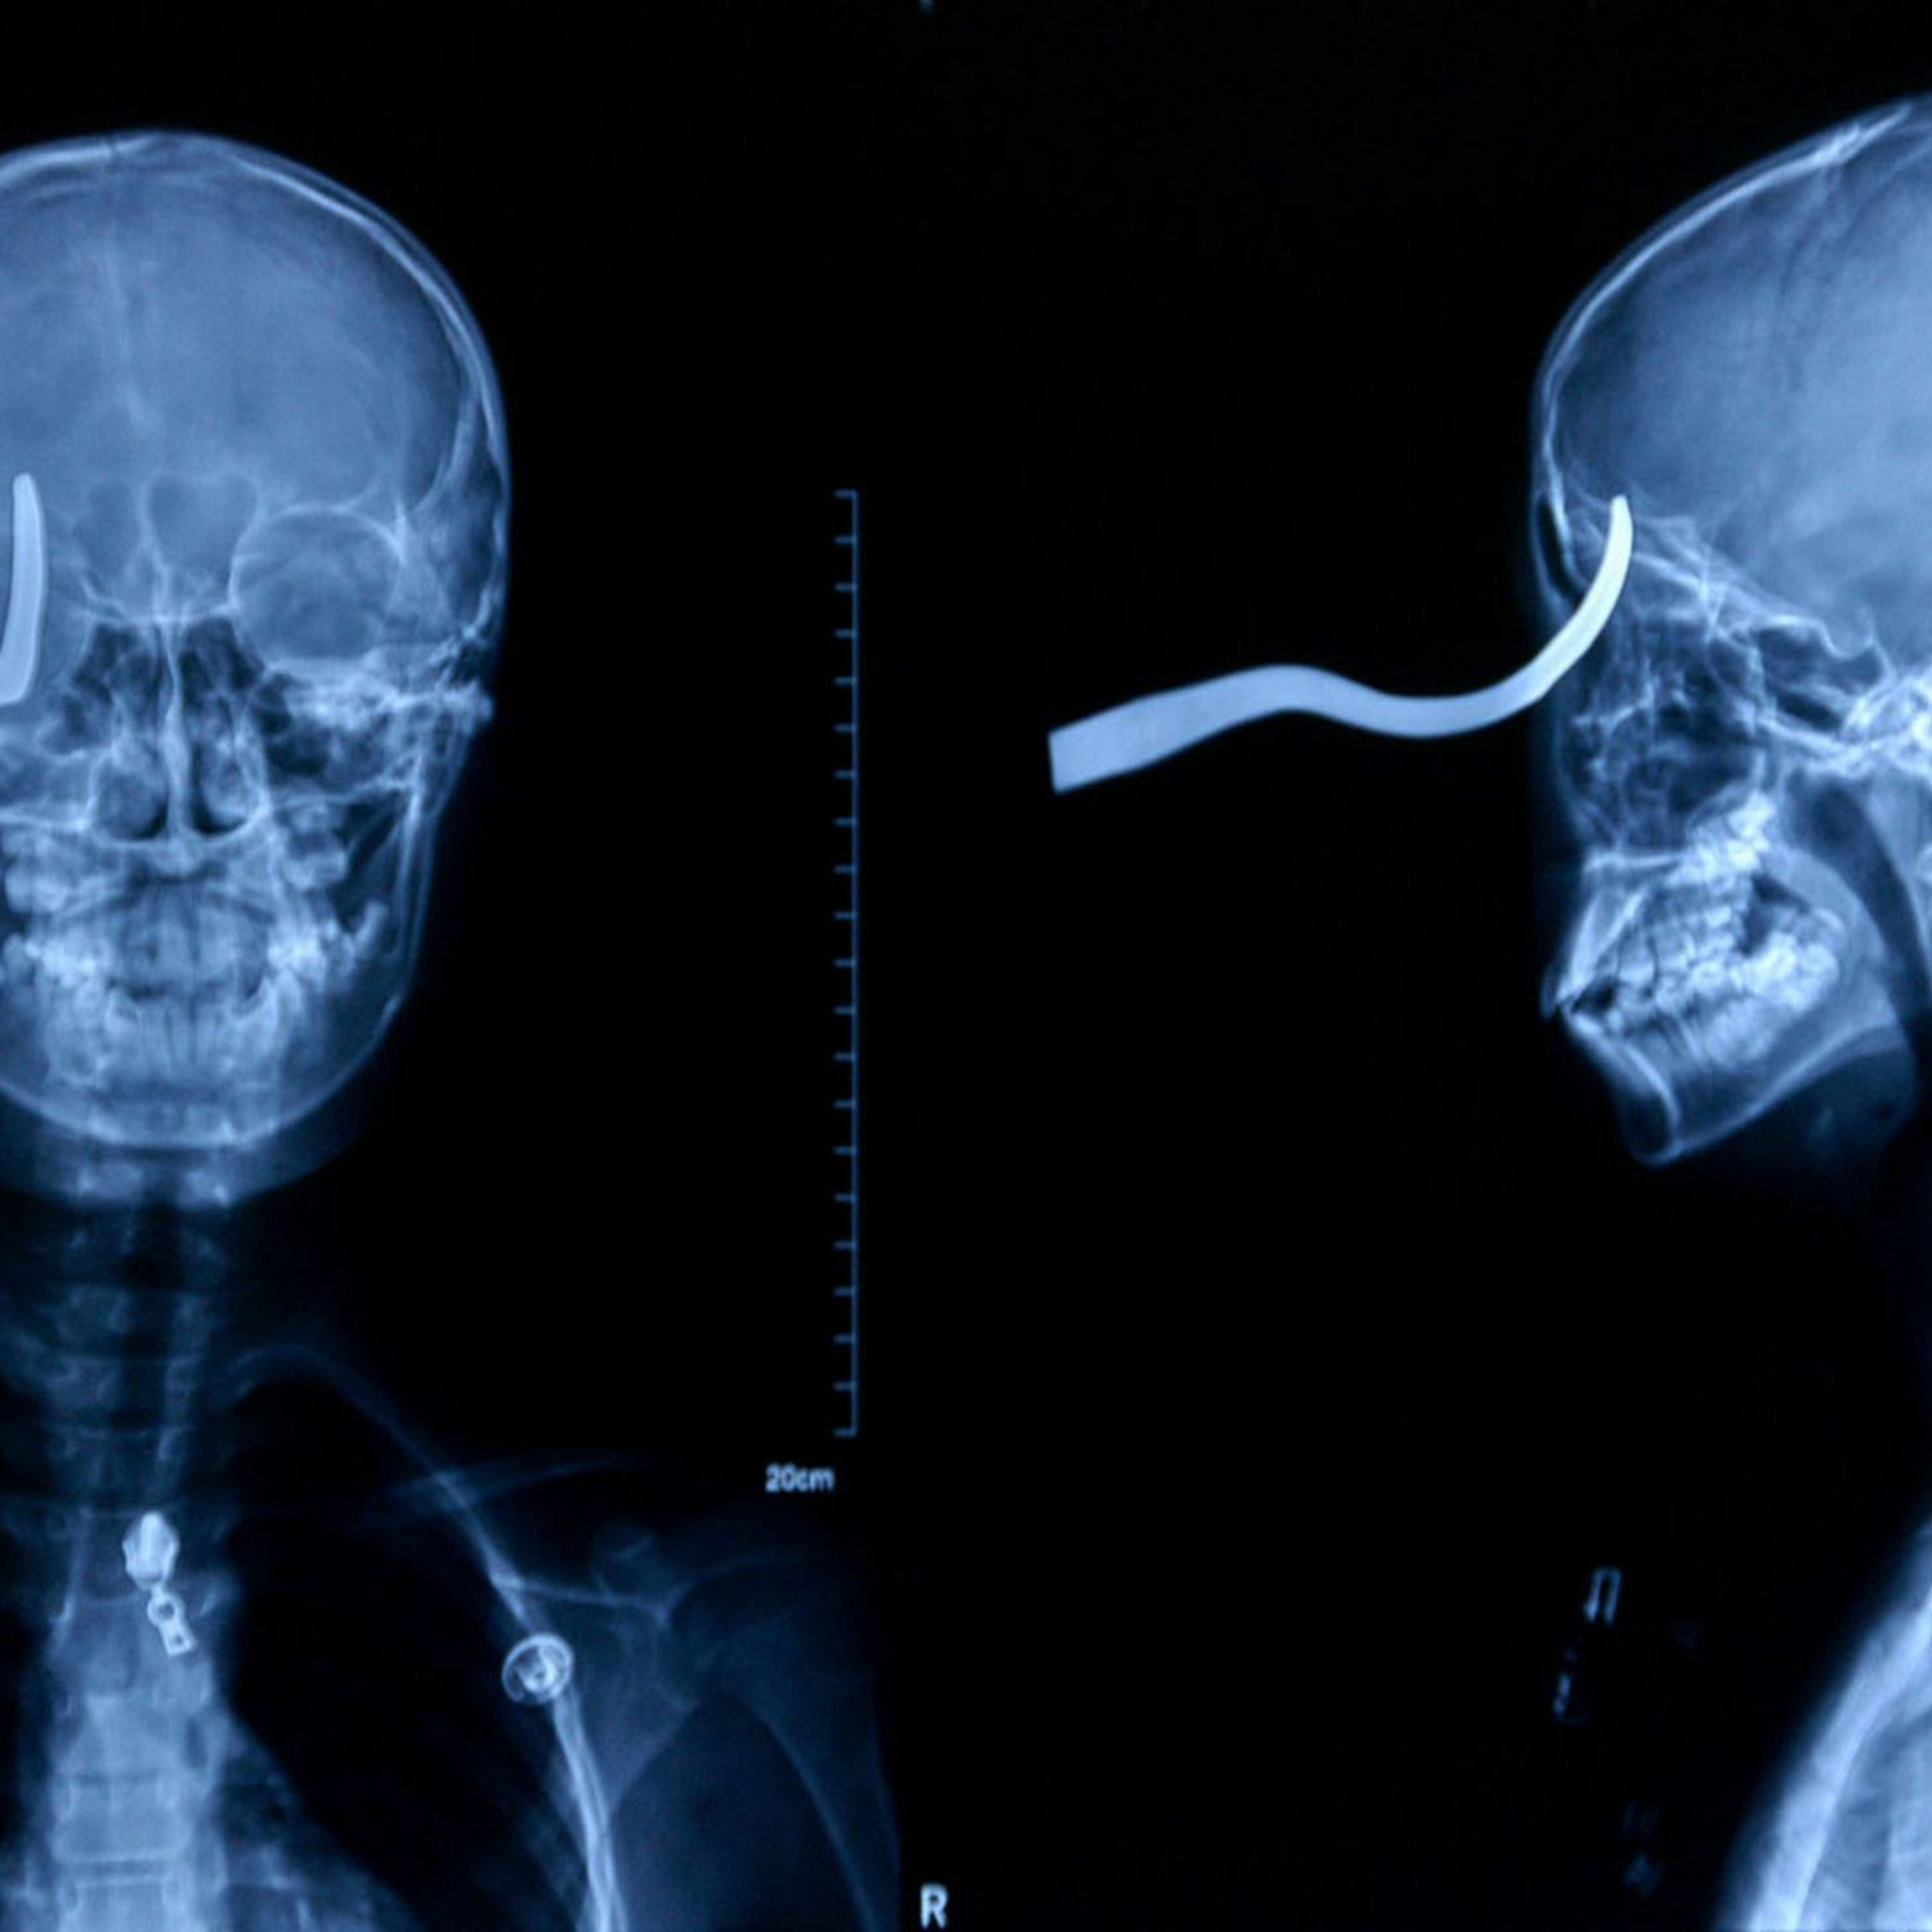

Chris and Mark discuss the long term effects of traumatic brain injuries and what's being done. The impact of such injuries are not always immediately visible and the consequences can be severe and long lasting. http://www.tbinrc.com/